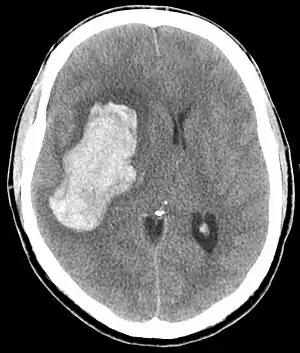

CT scan of an intracranial hemorrhage, a possible complication of hypertensive emergency.

Hypertensive emergency is very high blood pressure, generally a systolic above 180 mmHg, which is resulting in organ damage.[4][5] This may include stroke, hypertensive encephalopathy, acute aortic syndrome, acute coronary syndrome, retina disease, kidney problems, heart failure, pulmonary edema, or preeclampsia.[1]

The most common presentations of hypertensive emergencies are cerebral infarction (25%), pulmonary edema (23%), hypertensive encephalopathy (16%), and heart failure (12%).[8] Less common include intracranial bleeding, aortic dissection, and pre-eclampsia or eclampsia.[9]

In the brain, hypertensive encephalopathy - characterized by hypertension, altered mental status, and swelling of the optic disc - is a manifestation of the dysfunction of cerebral autoregulation. Cerebral autoregulation is the ability of the blood vessels in the brain to maintain a constant blood flow. People with chronic hypertension can tolerate higher arterial pressure before their autoregulation system is disrupted. Hypertensives also have an increased cerebrovascular resistance which puts them at greater risk of developing cerebral ischemia if the blood flow decreases into a normotensive range. On the other hand, sudden or rapid rises in blood pressure may cause hyperperfusion and increased cerebral blood flow, causing increased intracranial pressure and cerebral edema, with increased risk of intracranial bleeding.[11]